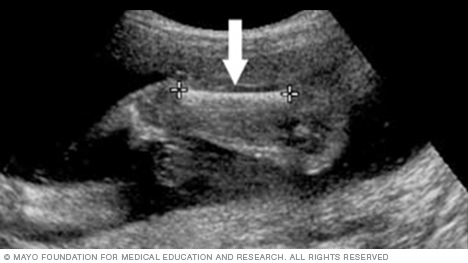

The image below shows all four chambers of the heart, as well as the heart valves. This type of image usually is taken during an ultrasound done between weeks 18 and 22 of pregnancy. Fetal ultrasound is used to check that the heart is working properly and to see if there could be any heart problems.